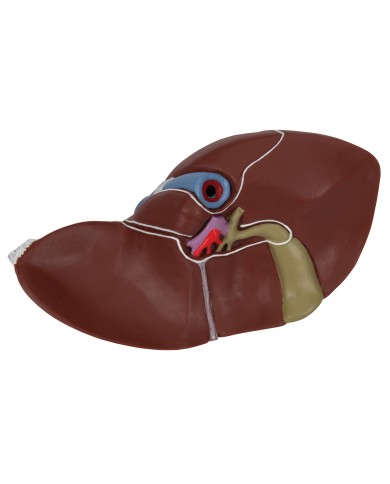

I Modelli anatomici 3B scientific ed Erler Zimmer sono quanto di meglio esista per studiare l'anatomia del corpo umano, il catalogo dei modelli anatomici comprende modelli di cranio, scomponibili, colorati, crani anatomici, crani su cavalletto, e il modello di punta, il cranio in 22 parti, ad incastro magnetico.

Questo e tanto altro ancora trovi nella sezione dedicata ai modellini anatomici, occhi, denti, orecchio, naso e gola, e i modelli anatomici per ostetricia e ginecologia, per lo studio dell'anatomia della pelvi e del bacino umano.

I modelli anatomici didattici sono riproduzioni di strutture anatomiche perfettamente uguali a quelle vere, i modelli di ossa sono realizzati dalla scansione di ossa vere, l'esperienza tattile è assolutamente realistica, ed anche il peso delle ossa corrisponde all'incirca al peso delle ossa vere.

Sono indispensabili per lo studio dell'anatomia umana, oggi è possibile osservare le strutture anatomiche senza la necessità di dissezionare cadaveri o di effettuare studi pericolosi su pazienti vivi.

Gli studenti di medicina utilizzano i modelli anatomici per i loro studi di anatomia umana, studiare l'anatomia sui libri non basta, un modellino anatomico permette uno studio molto più accurato che una foto o un disegno su un libro.

Medici, fisioterapisti, osteopati e professionisti sanitari utilizzano i modelli anatomici per dare spiegazioni ai pazienti sulle patologie, risparmiando tanto tempo prezioso durante la spiegazione, che diventa molto più efficace.